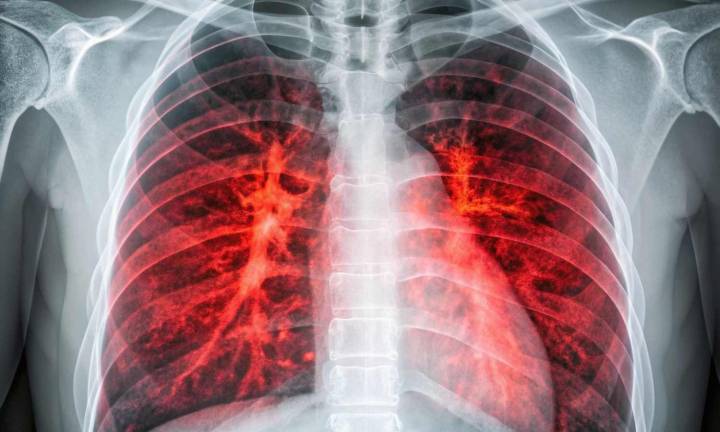

By creating high-resolution cellular and molecular visual maps of lung cancer before and during development, researchers at The University of Texas MD Anderson Cancer Center have discovered that the earliest stages of lung cancer may be driven by inflammation , suggesting that targeting proinflammatory pathways could be an early intervention approach.

The study, published today in Cancer Cell , generated spatial transcriptomic maps in precancerous and more advanced stages of lung cancer to provide a deeper understanding of early lung cancer development. The research was led by Humam Kadara, Ph.D., professor of Translational Molecular Pathology, and Linghua Wang, M.D., Ph.D., professor of Genomic Medicine, associate member of the James P. Allison Institute™ and focus area co-lead wit